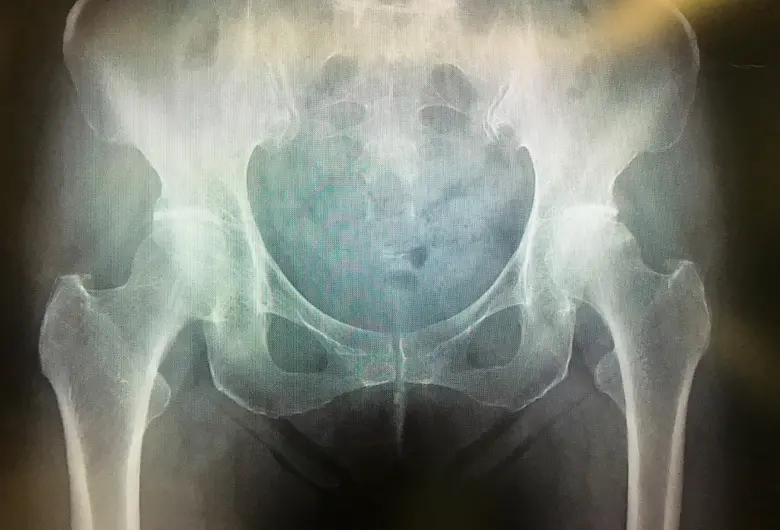

手術 人工股関節置換術(THA)

1: 人工股関節置換術(THA)

3: 手術方法と使用する人工関節

手術は股関節の前外側もしくは前方からアプローチし、筋肉を切らずに筋肉を分けて関節に到達します。

関節軟骨が傷んだ部分を切除し、人工関節を正しい位置に設置します。

レントゲン検査やCTによる事前検査を通じて患者さんの骨質・骨形状に最適なインプラントを選定します。